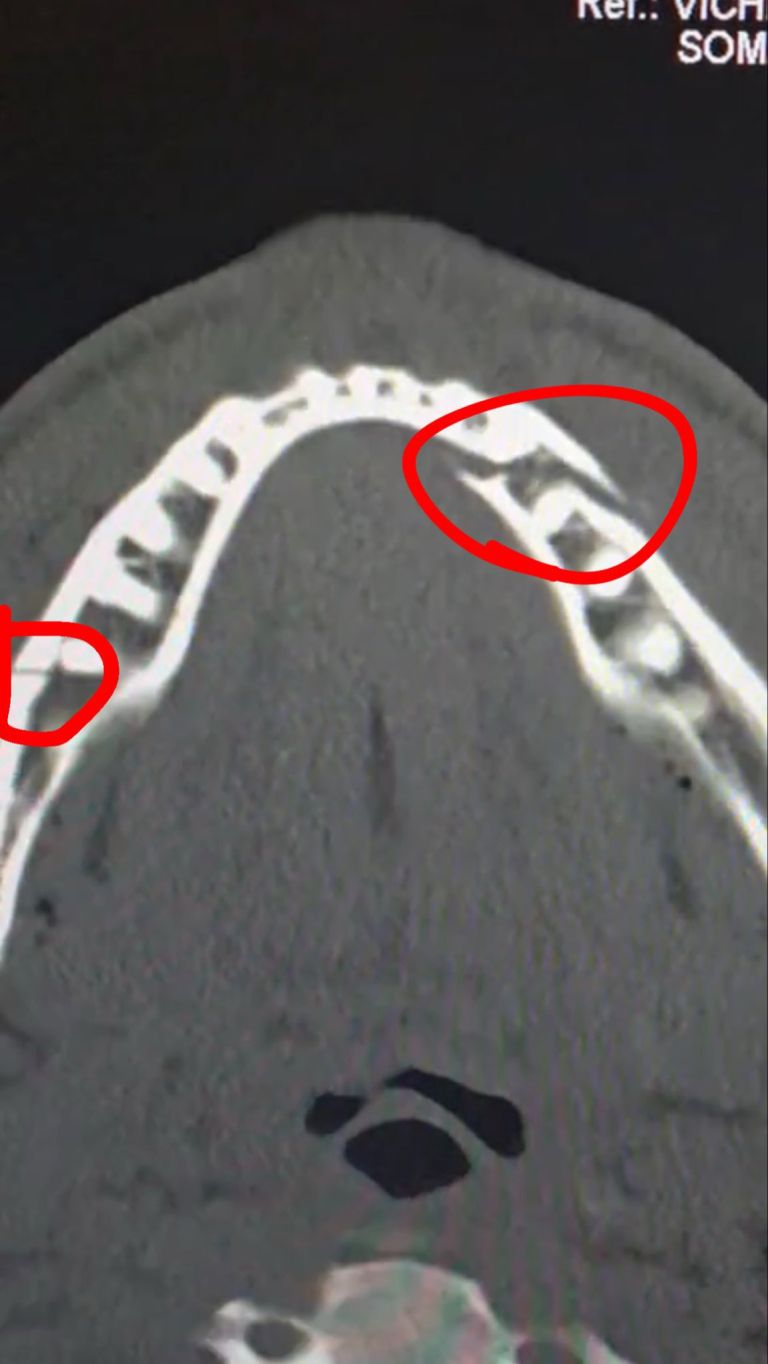

Po spletu je zaokrožila fotografija, ki razkriva, da mu je Joshua premaknil zobe na spodnji čeljusti, kar je seveda nakazovalo na zlom, rentgenska fotografija pa je razkrila, da gre v resnici za dvojni zlom.

Paulu so poškodbo že sanirali, mu vstavili dve titanski ploščici, odstraniti pa so mu morali tudi več zob na spodnji čeljusti. V naslednjem tednu se bo moral prehranjevati po slamici, se bo za zato lahko tolažil s skoraj 90 milijoni evri, kolikor jih je dobil za omenjeni dvoboj v Miamiju.